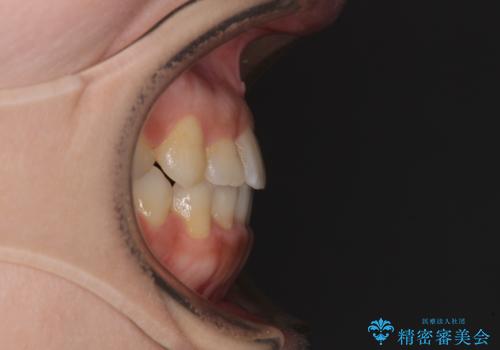

前歯のクロスバイトと変色した歯 ワイヤー矯正とセラミック治療

- 前歯のクロスバイトと神経を取り除いた後に変色してしまった前歯を気にして来院された患者様です。

変色してしまった前歯は、反対側の歯と比べて歯肉が覆い被さっていたため、骨整形を含めた歯周外科処置を行い、歯肉ラインを整えることとしました。